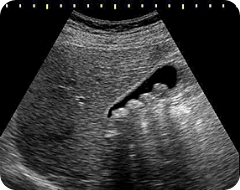

The first test to be requested in suspected cases of Cholelithiasis is the ultrasound. With the help of Ultrasound stone can be seen:TREATMENT: